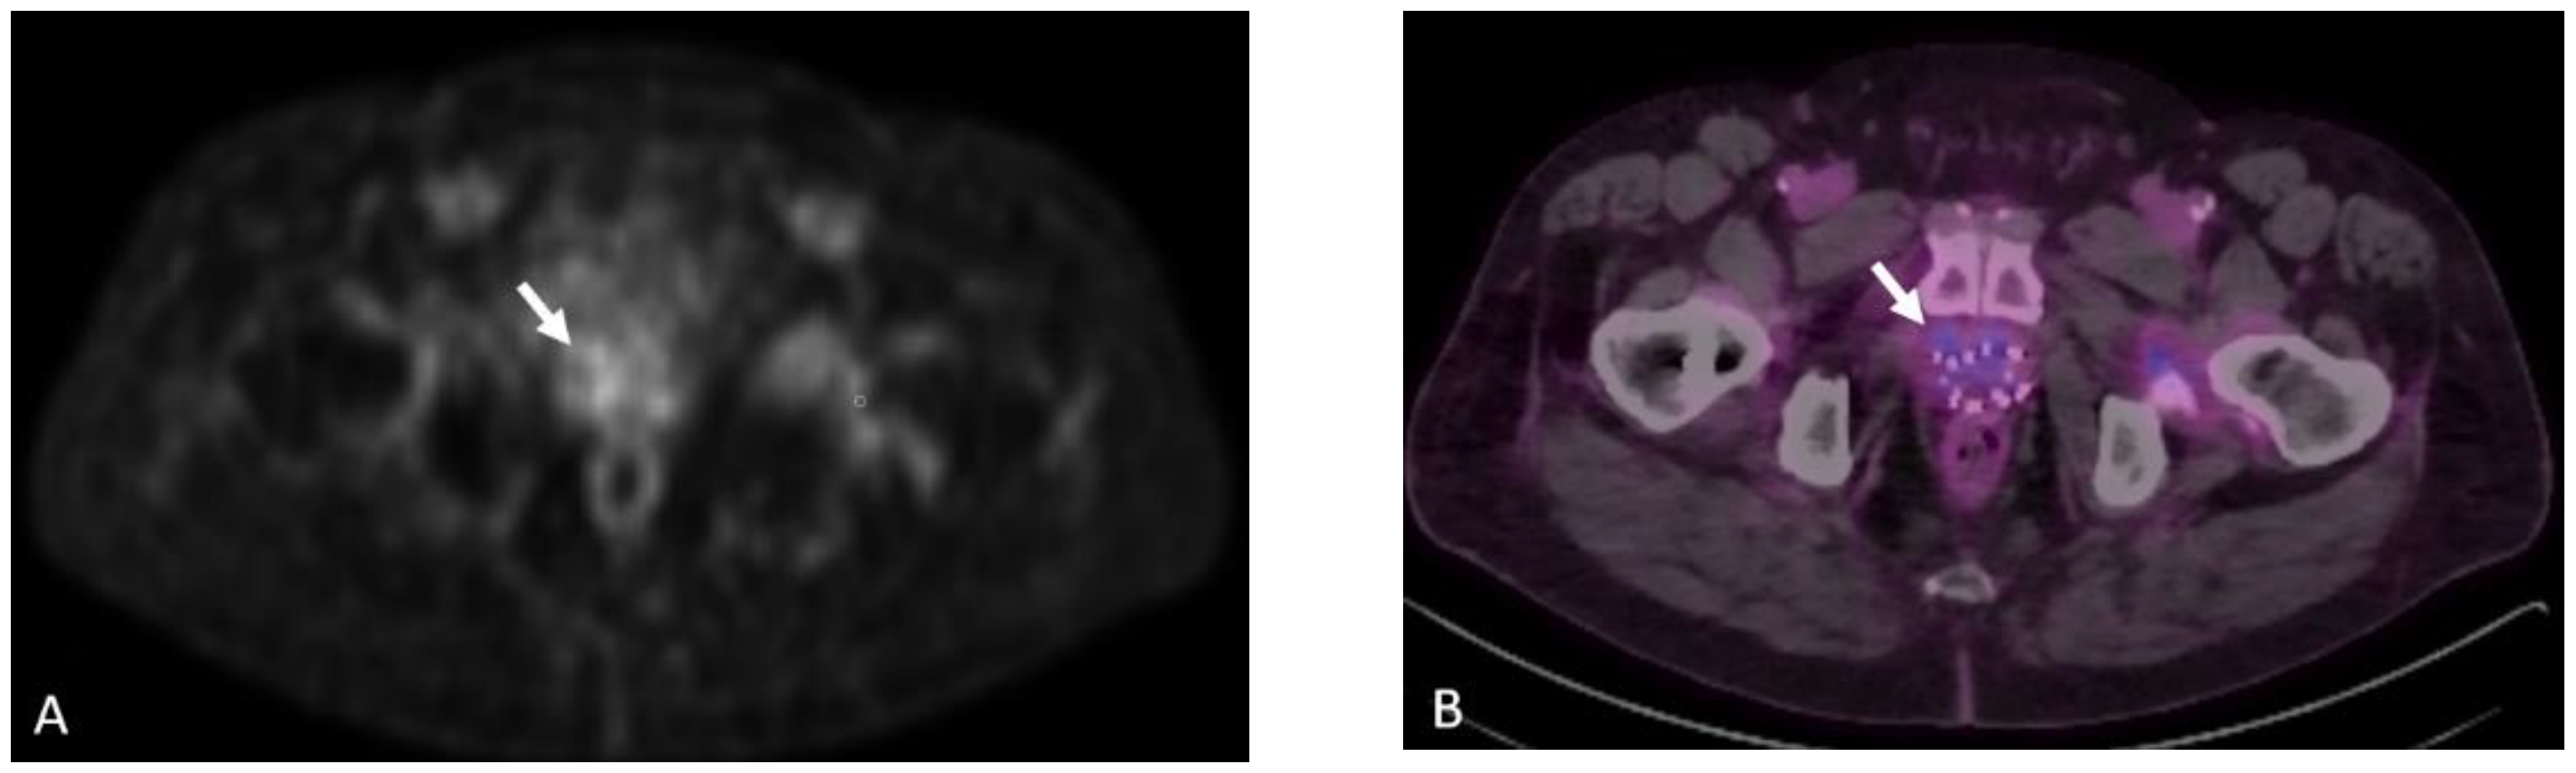

Detection of Loco-Regional Disease and Distant Metastases

Detection of Loco-Regional Disease and Distant Metastases

1.9.3. Pearls and Pitfalls